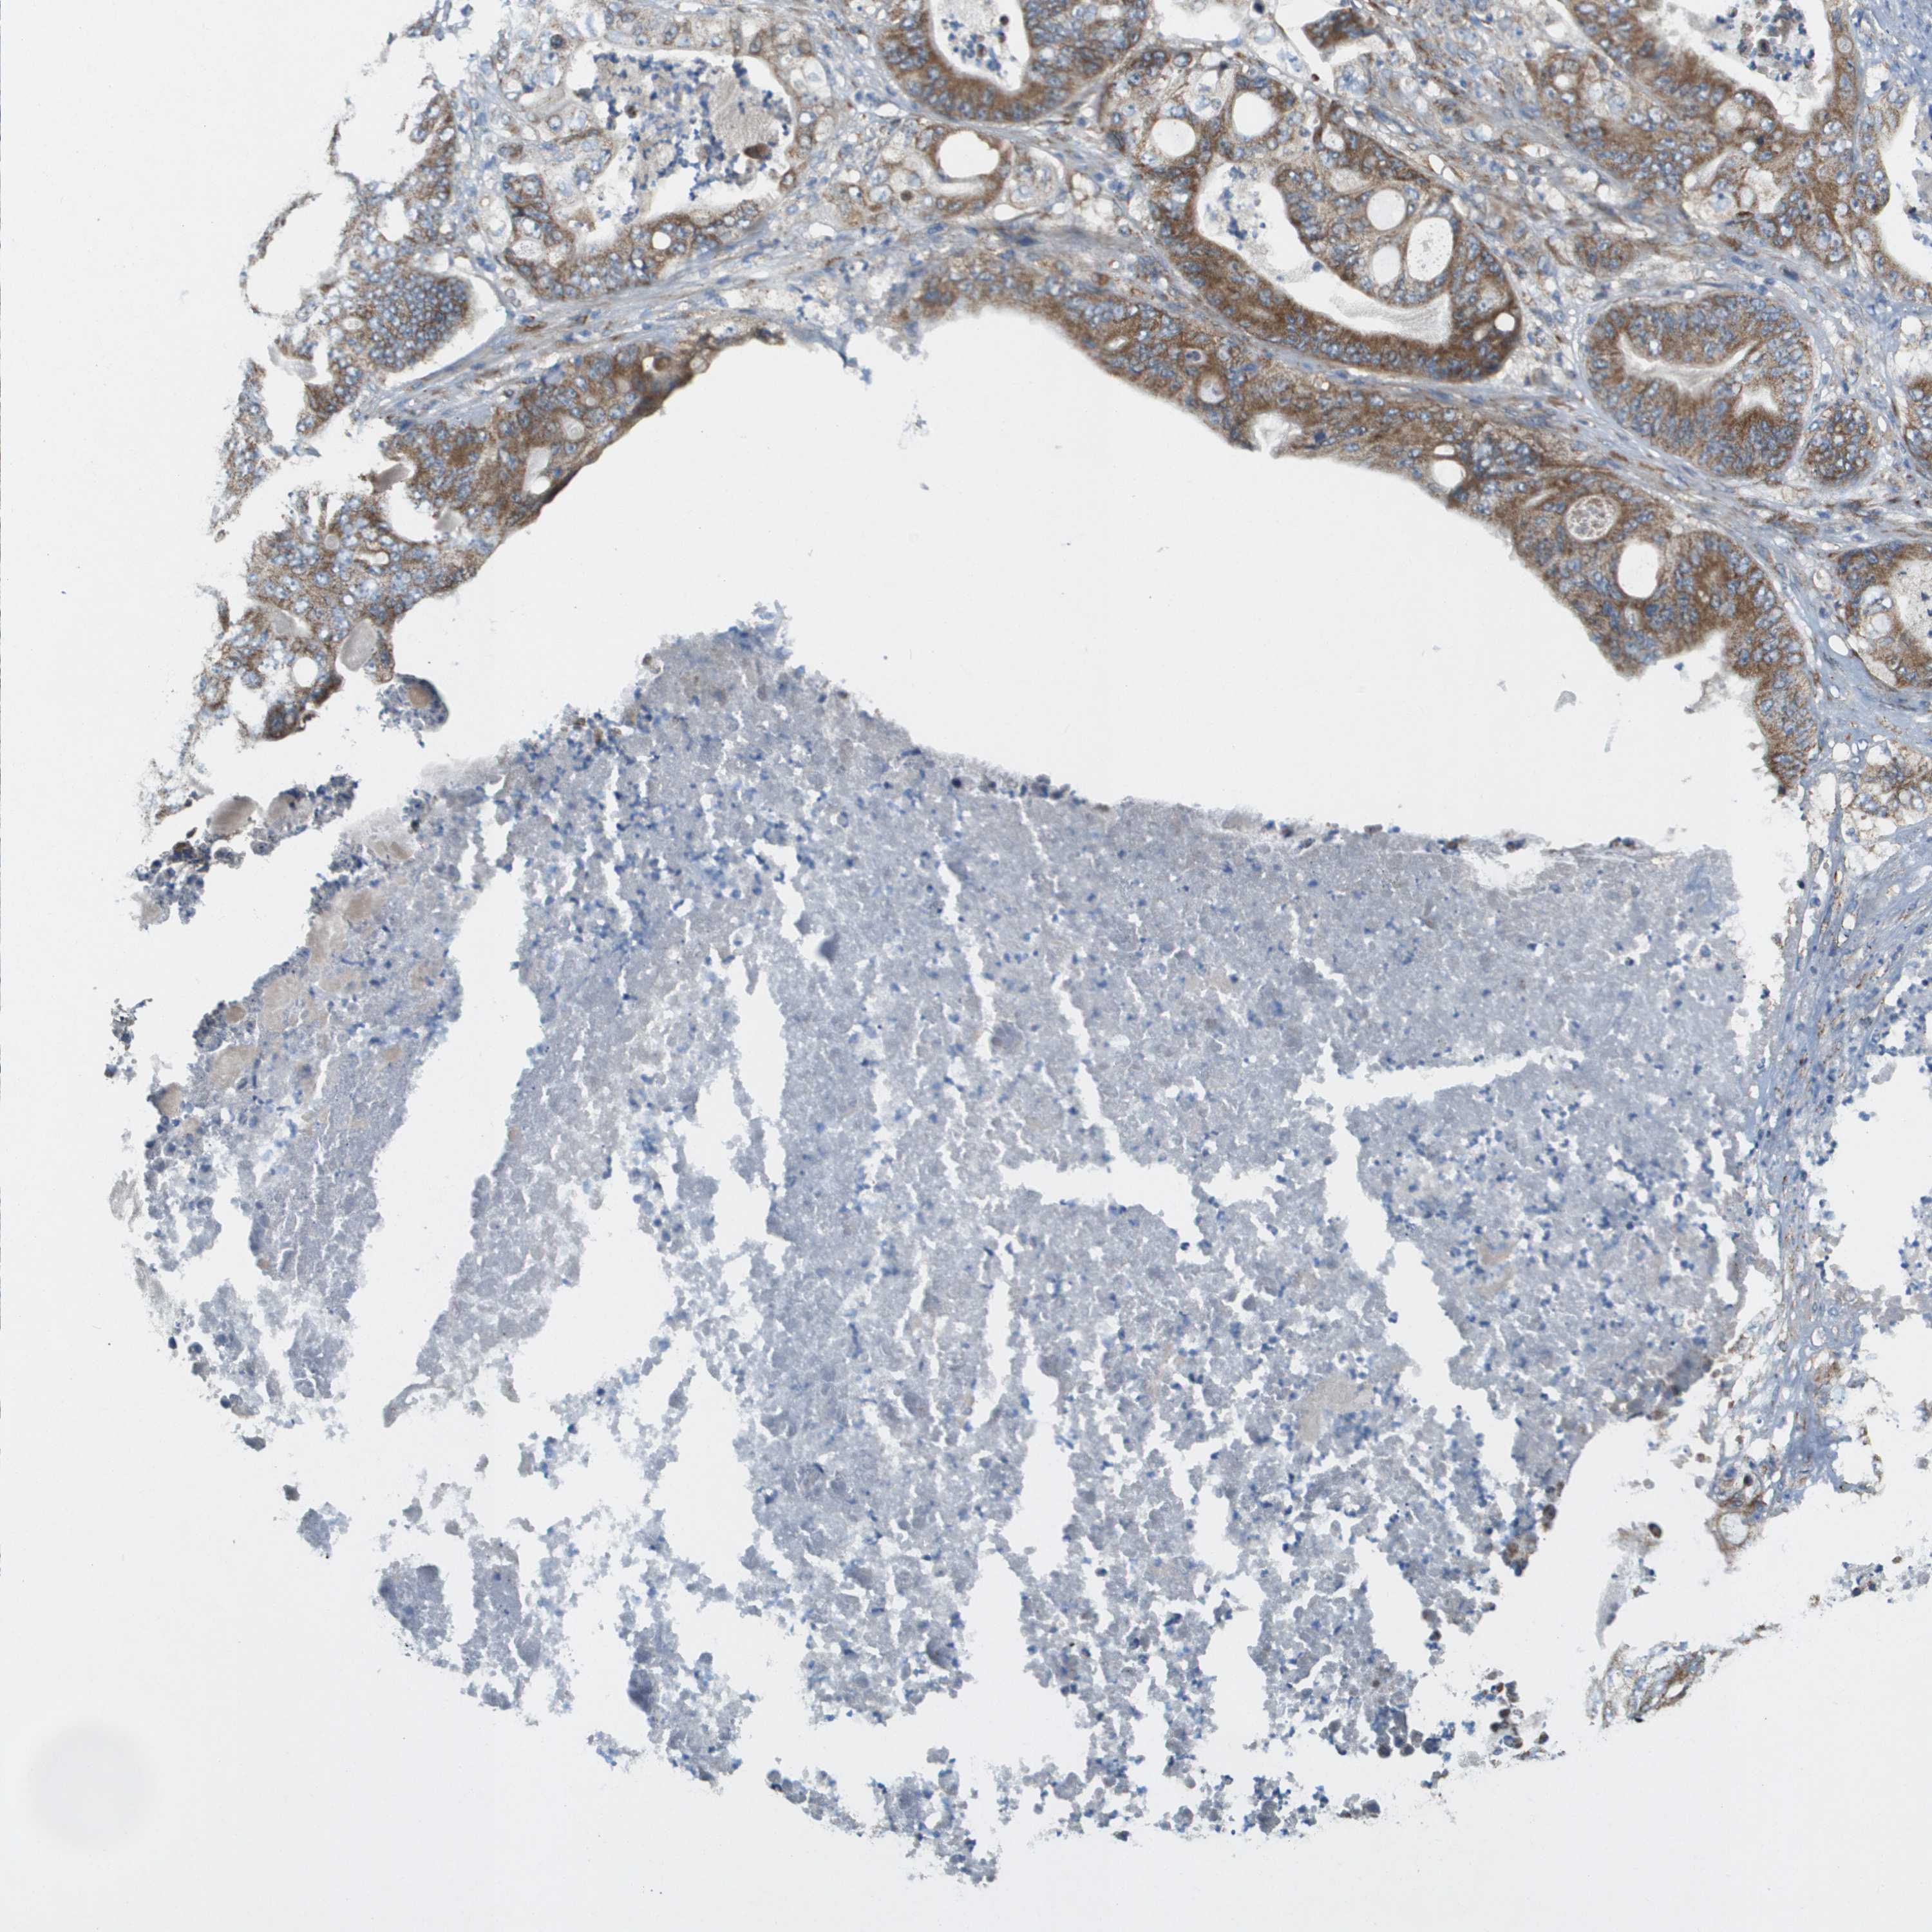

STOMACH CANCER - Protein expressioni

A mouse-over function shows sample information and annotation data. Click on an image to view it in a full screen mode. Samples can be filtered based on level of antibody staining by selecting one or several of the following categories: high, medium, low and not detected. The assay and annotation is described here.

Note that samples used for immunohistochemistry by the Human Protein Atlas do not correspond to samples in the TCGA dataset.

Antibody stainingi

Antibody staining in the annotated cell types in the current human tissue is reported as not detected, low, medium, or high, based on conventional immunohistochemistry profiling in selected tissues. This score is based on the combination of the staining intensity and fraction of stained cells.

Each image is clickable and will lead to virtual microscopy that enables deeper exploration of all samples and also displays staining intensity scores, fraction scores and subcellular localization as well as patient and tissue information for each sample.

Antibody HPA017238

Staining

High

Medium

Low

Not detected

Intensity

Strong

Moderate

Weak

Negative

Quantity

>75%

75%-25%

<25%

None

Location

Nuclear

Cytoplasmic/membranous

Cytoplasmic/membranous,nuclear

Adenocarcinoma, NOS